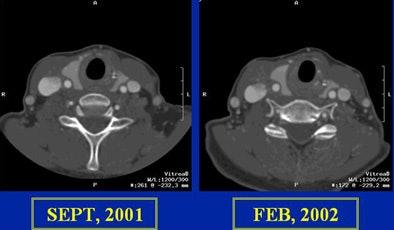

Plugging CTA at the end, Cinnamon said the modality can provide information and views, such as those found in multitissue displays, that are simply unavailable in other modalities. In a patient with an ICA stent, CTA showed the development of neointima, a predictor of restenosis, at the site on follow-up images, he said.

![]() |

| In a patient with an internal carotid artery (ICA) stent, CTA showed the development of neointima, a predictor of restenosis. |